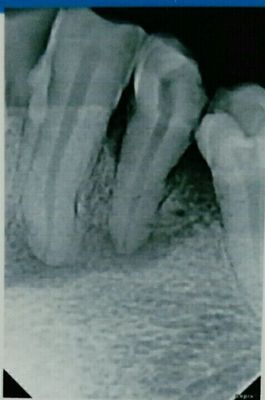

口腔内左下第三第四龋齿 X线片 示 慢性根尖周炎(见图)